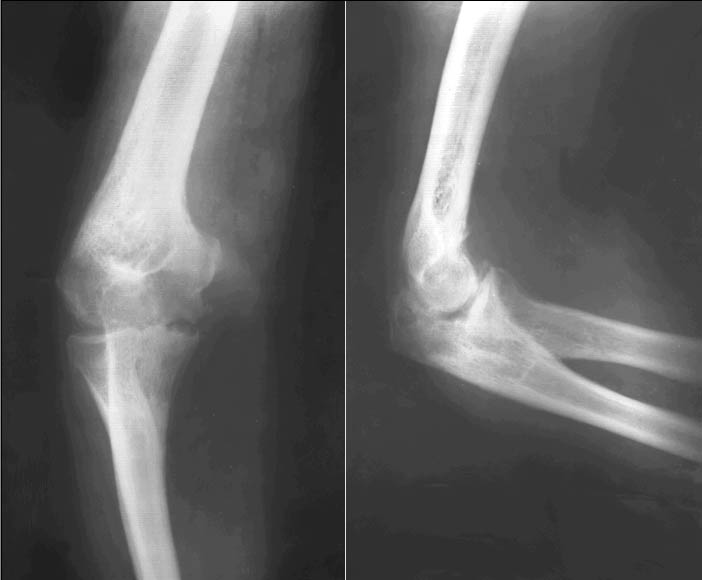

Поставить точный диагноз, основываясь только на жалобах пациента, сложно, а определить стадию остеоартроза еще труднее. Поэтому в медицинских учреждениях часто назначают рентгенографию или магнитно-резонансную томографию.

На рентгеновских снимках изменения в суставах становятся заметными даже на первой стадии заболевания. Врач обращает внимание на сужение суставной щели между элементами сустава.